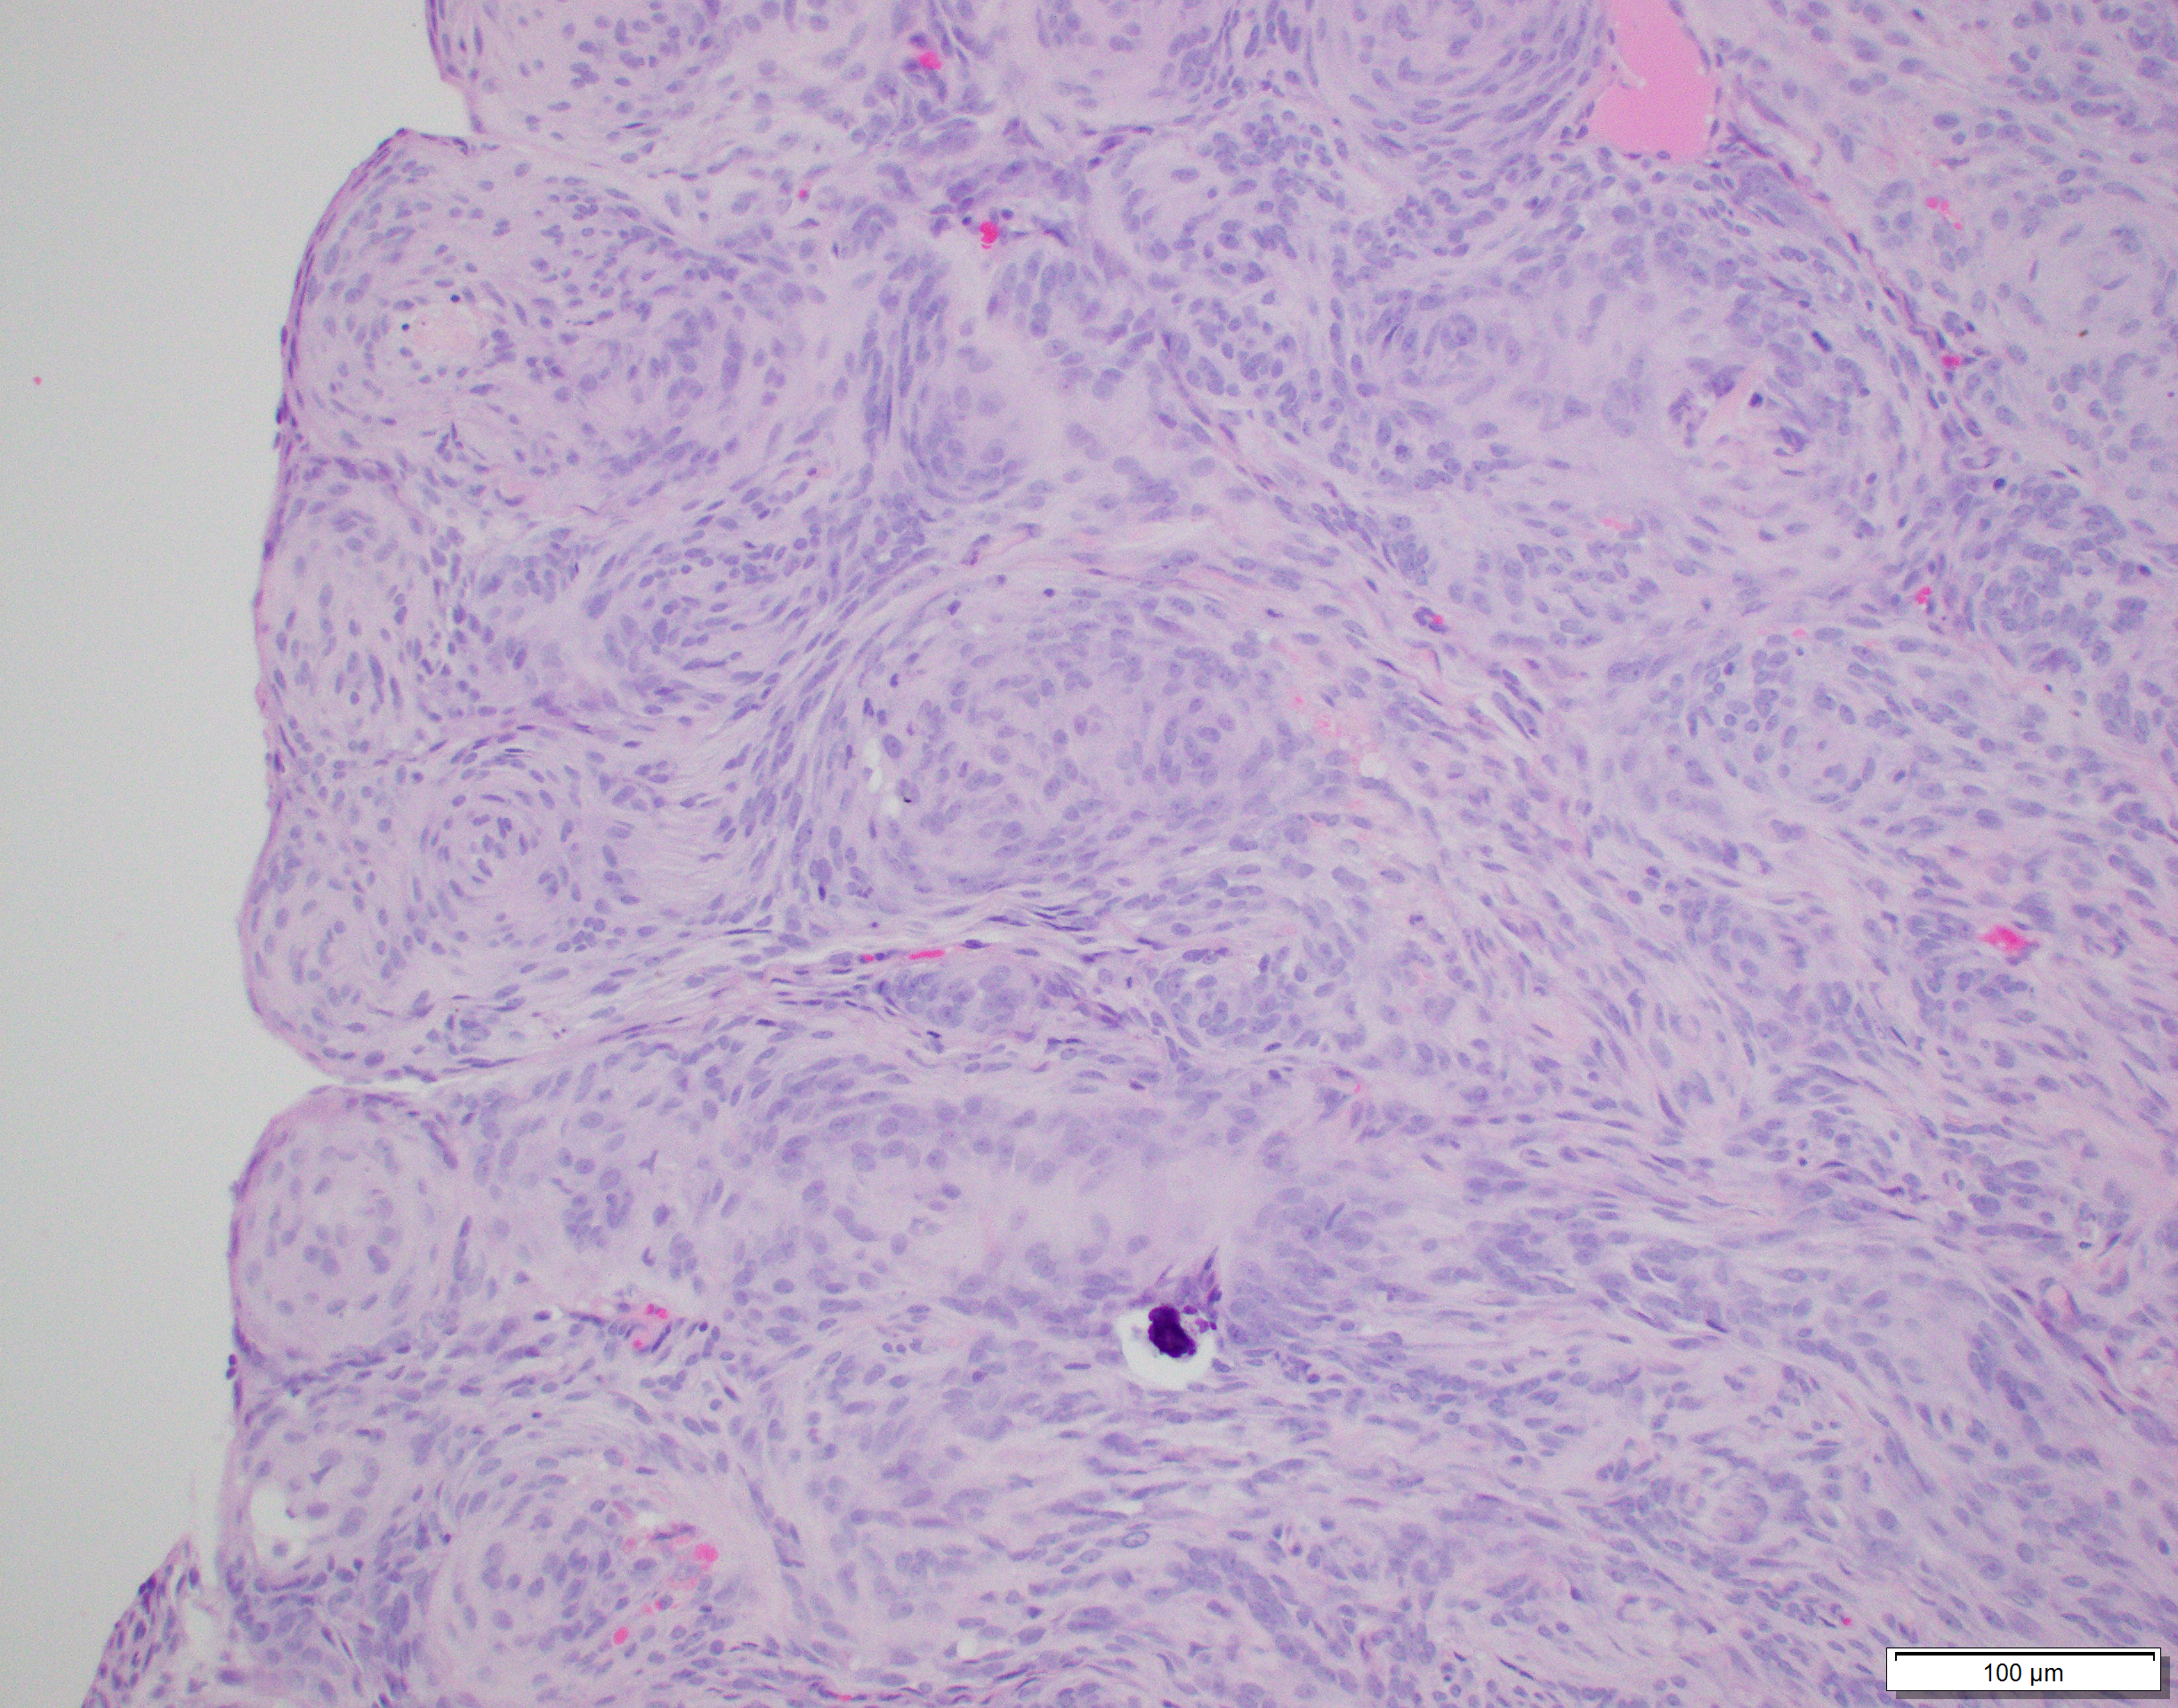

Histology:

The cat underwent successful surgical resection of the intracranial mass. Based on the pathology samples shown below, what is the most likely anatomic diagnosis?